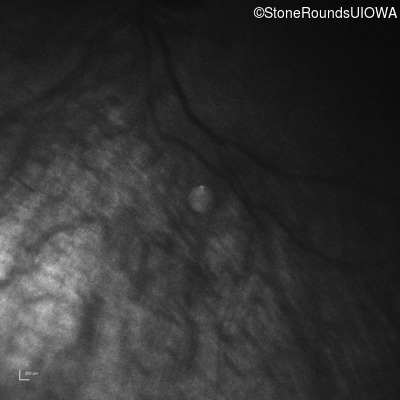

Infrared Fundus Photograph - Right -

No Light Perception

Exemplar

Expanded OCT Stack

×